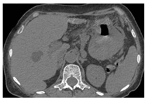

患者 女性,61岁,因上腹部不适7个月加重伴反复呕血、黑便2 d,于2014年10月16日来我院就诊,发病过程中无发热。查体:贫血貌,皮肤黏膜苍白,浅表淋巴结未触及肿大,腹平坦,未见肠型及蠕动波。血细胞分析(全血分类):红细胞计数3.38×1012/L、血红蛋白89.00 g/L、白细胞计数6.08×109/L、淋巴细胞计数1.03×109/L、淋巴细胞比率16.92 %。肝功能检查示:丙氨酸氨基转移酶4.40 U/L、天门冬氨酸氨基转移酶10.90 U/L、总蛋白64.40 g/L、清蛋白(A) 34.40 g/L、球蛋白(G)30.00 g/L、A/G 1.15、β2-微球蛋白(β2-MG) 4.59 mg/L。免疫球蛋白及骨髓穿刺未见异常。胃镜示:胃体下部至胃窦近幽门口见有结节状肿物,边界不清,胃窦腔狭窄、僵硬,肿物表面溃疡糜烂,见有红黑色血迹,散在溃疡,覆有灰白苔,组织硬,脆,易出血。CT检查结果示:胃体处胃壁明显增厚改变,胃腔狭窄;周围可见淋巴结影,脾脏增大,密度均匀(图1)。无传染病史,行下部胃大部+网膜切除术。病理检查结果:胃大弯长24.5 cm,小弯长6.0 cm,上切缘直径6.0 cm,下切缘直径2.0 cm,胃体大弯侧见肿物10 cm×7 cm×6 cm,肿物向胃腔内结节状生长,周边呈溃疡状,切面灰白,质嫩,浸润胃壁肌层,大网膜组织与胃浆膜层广泛粘连,胃周脂肪组织见肿大淋巴结9枚,直径0.2~ 2.0 cm。显微镜下观察:大淋巴细胞样相似于免疫母细胞的瘤细胞弥漫浸润,分布于胃壁,最深达深肌层,组织伴大面积坏死。细胞形态单一,胞质丰富,细胞核大而圆,染色质粗,核仁小,有的不明显,见浆样分化的细胞,核分裂象易见,可见凋亡小体及吞噬可染小体的巨噬细胞(图2)。免疫组织化学示:MUM-1+(图3)、CD20-、CD3-、bcl-2-、CD8-、CD30-、CD38-、CD138-、CD10-、bcl-6-、CK-、Ki-67 60 %+、CD21-。原位杂交EBER结果阳性。病理诊断结果:胃体大弯非霍奇金浆母细胞淋巴瘤(PBL),胃周淋巴结转移(2/9)。